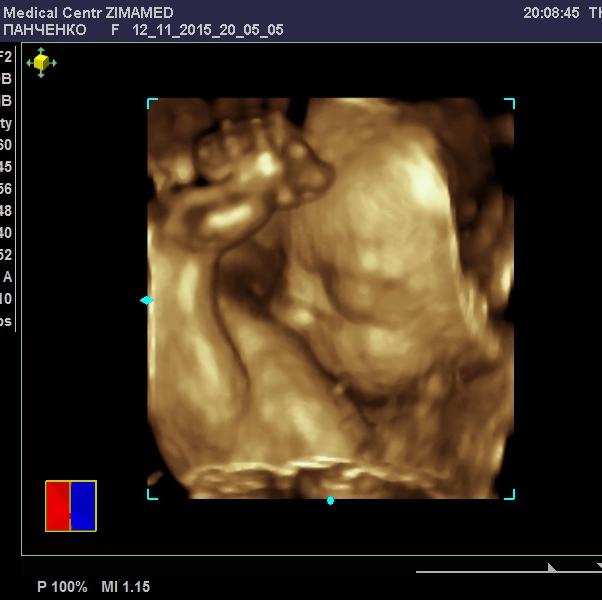

Девочки, вчера мы наконец сходили на 3D. это чудо!! Посмотрели на дочу 😍 Правда она взяла ноги в руки и закрыла лицо😄😄😄 долго вылавливали ее.. но впечатлений осталась куча. Анечка с удовольствием смотрела на сестричку, восторгалась маленьким ножкам и ручкам 😍. уже понятно, что малышка будет очень на нее похожа и такая же курносая 😄 обе дочи- папины копии. Еще одна хорошая новость, что мой рубец за 5 недель не изменился и остался в районе 3мм. Это немного меня успокоило. Врач сказала, что даже тонкий рубец может быть состоятельным 👌 что ж, будем наблюдать его и дальше.. Всем хорошего настроения и моря положительных эмоций!!!!😙

@linchster, сверху-это моя фамилия. запись на диск 4D и фотки (без скрининга) стоят 1100. оплата после процедуры, т.к. может с первого раза не получиться.

@morganita, это Бабаева вам делала? Просто сверху Панченко написано) а сколько 3д вам вышло? Я должна была 9го к ней пойти, но меня направили в этот же день в 5ый роддом. Я все равно хочу к ней сходить после 2 скрининга

@linchster, в зимамеде врачи рекомендуют в 28-30 недель. говорят, что красивее всего малыш смотрится, что якобы уже жирок появляется и черты лица лучше видно. Вообще, я там очень довольна врачом Бабаевой, она супер специалист 👍 постоянно к ней ходим, все старательно делает.